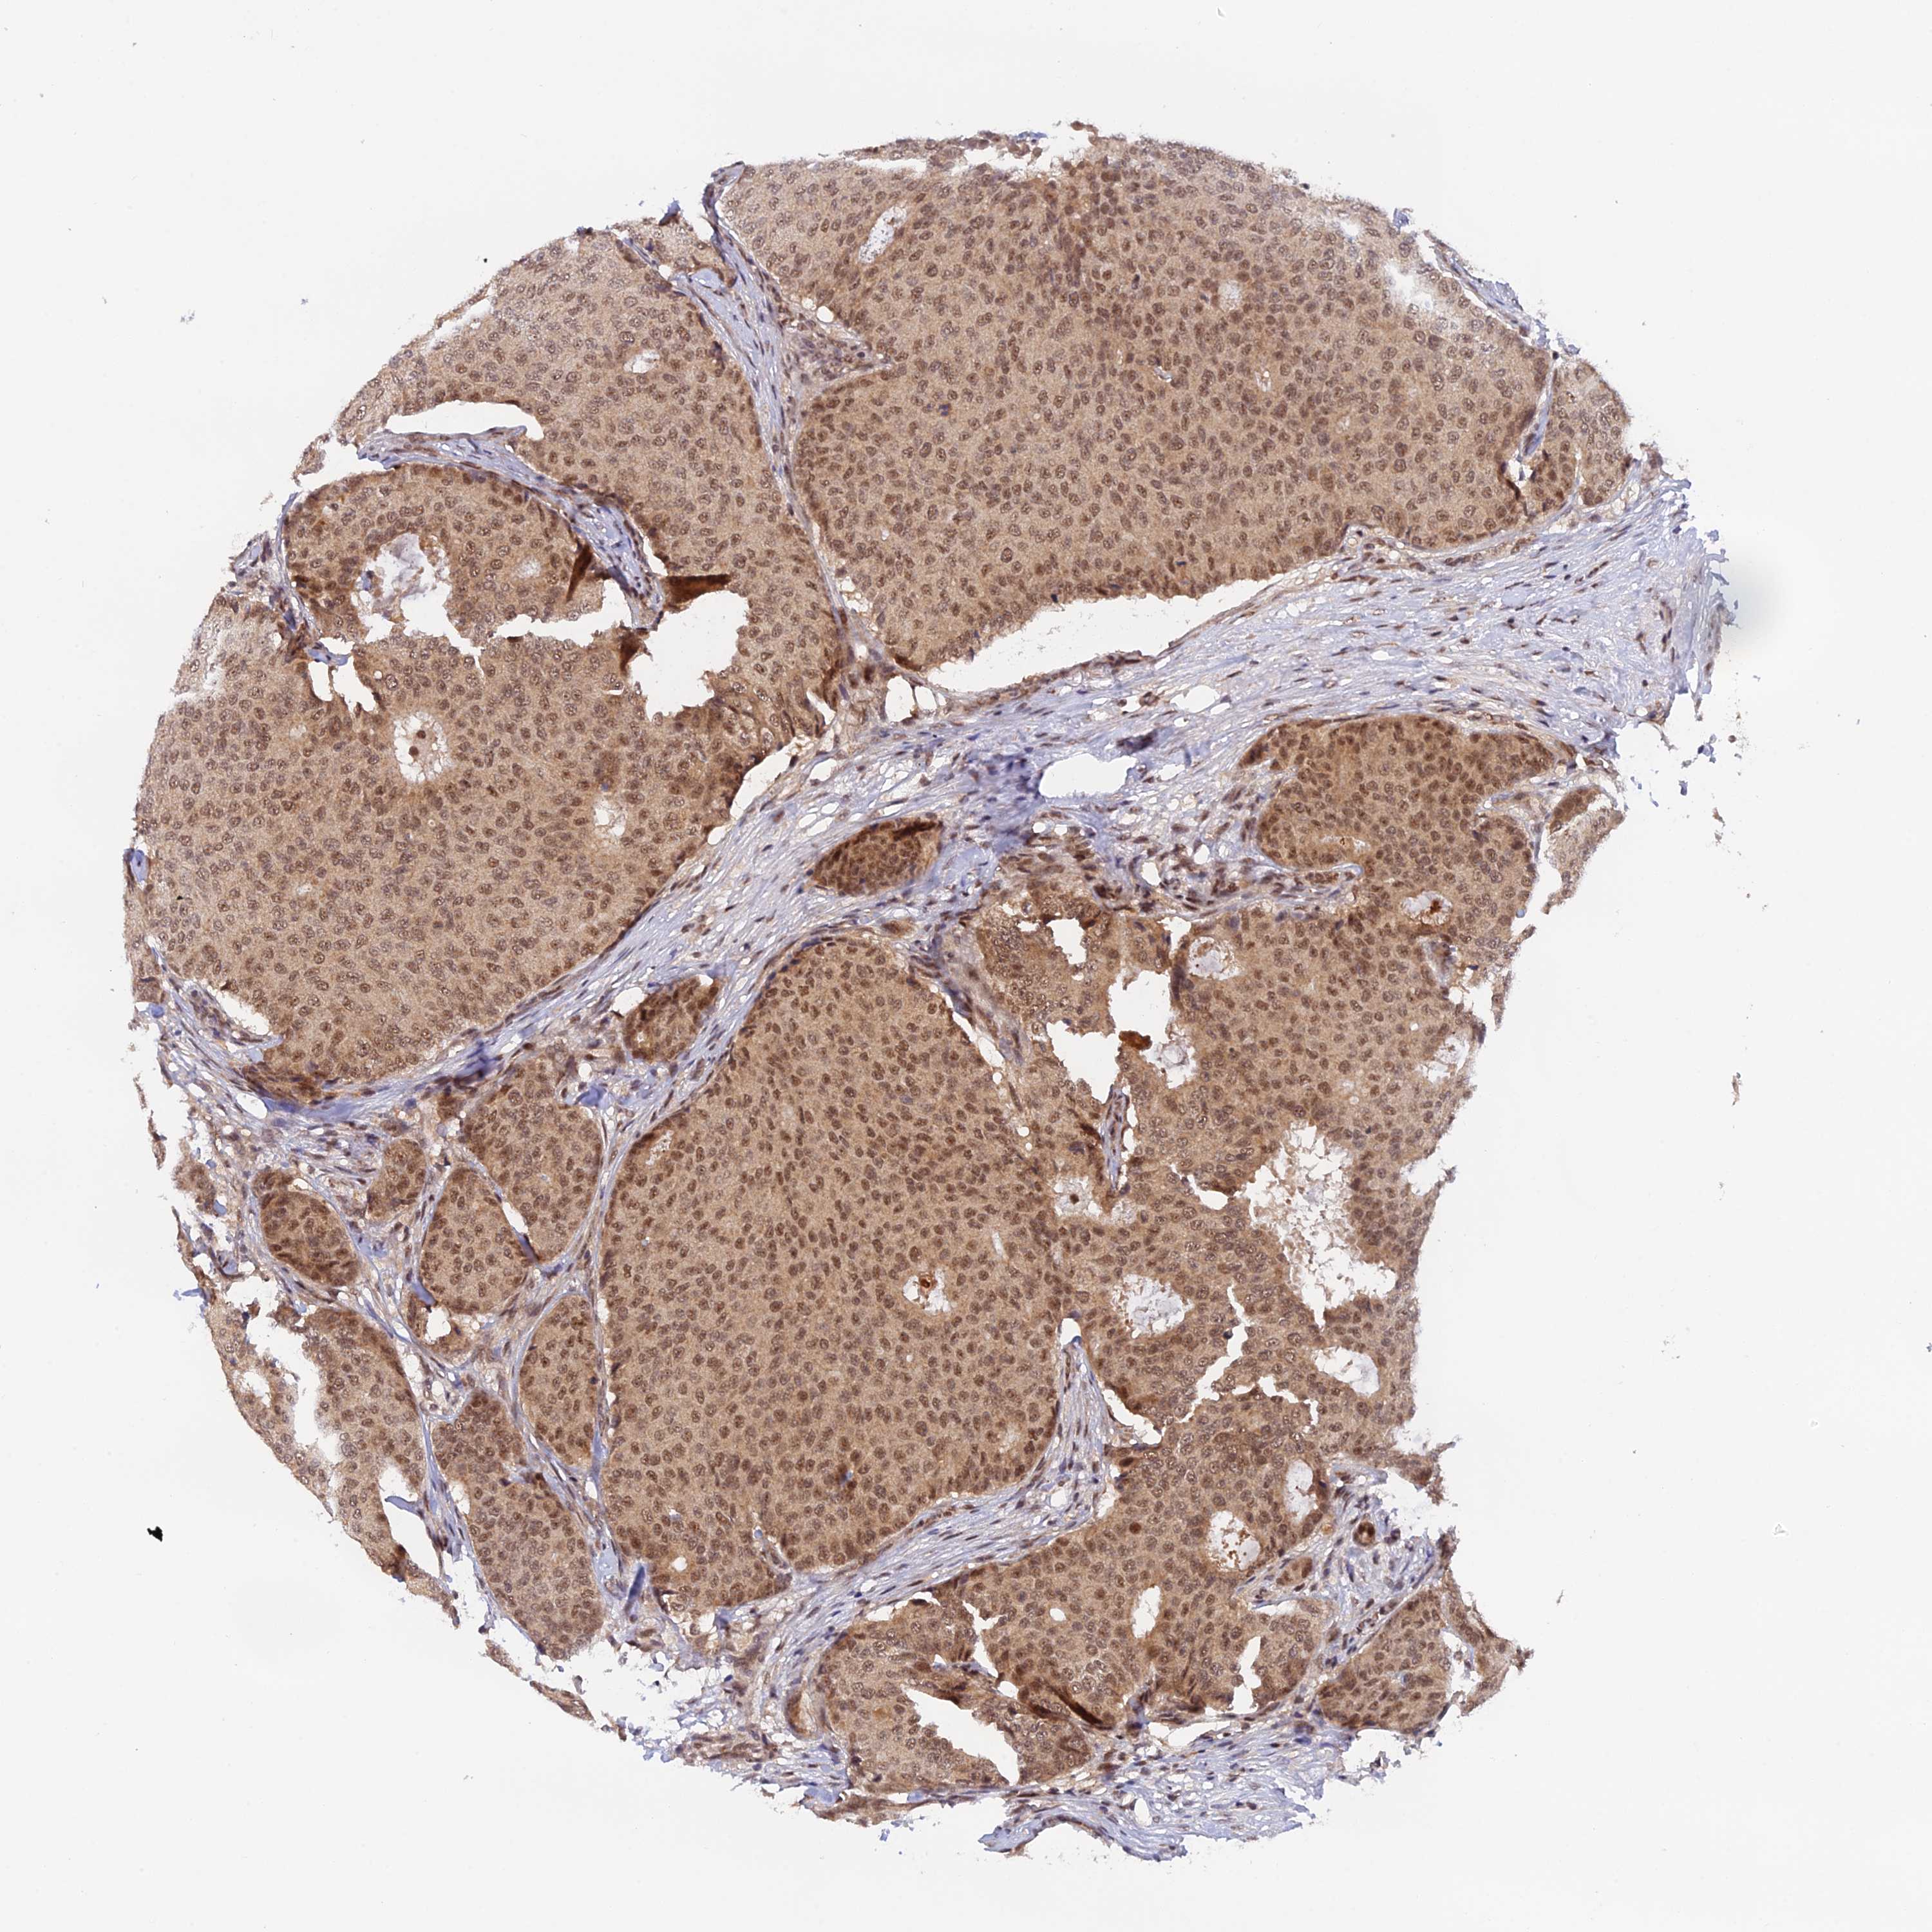

BRCA TCGA BRCA VALIDATION PROTEIN EXPRESSION

ANTIBODIES

AND

VALIDATION